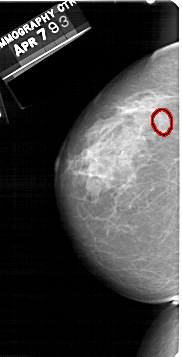

A_1512_1.RIGHT_MLO

RIGHT_MLO LINES 5491 PIXELS_PER_LINE 3046 BITS_PER_PIXEL 12 RESOLUTION 43.5 NON_OVERLAY

FILE: A_1512_1.LEFT_CC.OVERLAY

TOTAL_ABNORMALITIES 1

ABNORMALITY 1

LESION_TYPE MASS SHAPE OVAL MARGINS CIRCUMSCRIBED

ASSESSMENT 3

SUBTLETY 4

PATHOLOGY BENIGN

TOTAL_OUTLINES 1

BOUNDARY